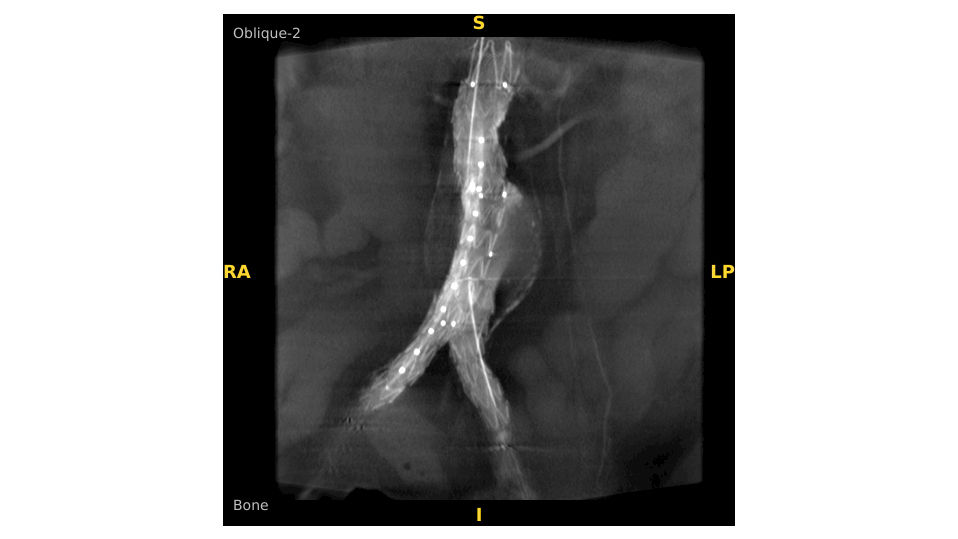

Analysieren Sie Ihre Scans mit dem GE Volume Viewer – genauso intuitiv wie am CT. Profitieren Sie von der vollständigen Darstellung axialer, koronarer und sagittaler Ebenen sowie von MIP-Ansichten und 3D-Visualisierungen im VR-Modus. Scrollen Sie durch bis zu 512 Schichten mit nahtloser Anpassung der Schichtdicke – für eine präzise Befundung direkt im OP.